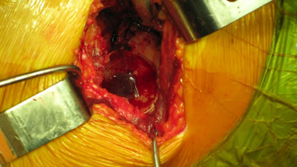

Modified Anterior-lateral Watson-Jones surgical approach. |

Cup orientation and preparation is challenging and care should be taken not to penetrate the medial wall. Proper cup placement is difficult do to loss of bony landmarks. Hip abductors will be weak and joint instability is a significant concern. Lateralization of the femoral component will aid in reducing forces across the hip joint potentially reducing limp and post-operative hip dislocation.

| Pre-operative consideration was discussed on shorting the stem to avoid any potential femoral canal perforations. For this reason a special proximal modular stem “Dual-Press” design was utilized. Proximal conical reaming was done without the use of a pilot shaft along with rasping of the femoral triangle. |

Careful intra-operative measurements were done then surgery on the stem to customize “shortening of the stem” stem length. |

| The stem fit was excellent with impressive implant to bone stability. The proximal modular neck design allowed selection of a variety of femoral offsets and neck lengths. This along with large head M-O-M (40mm) bearings provided significant ROM and hip joint stability. The short stem functions as a pilot with implant to bone stability provided by proximal stem geometry (cone & triangle). |